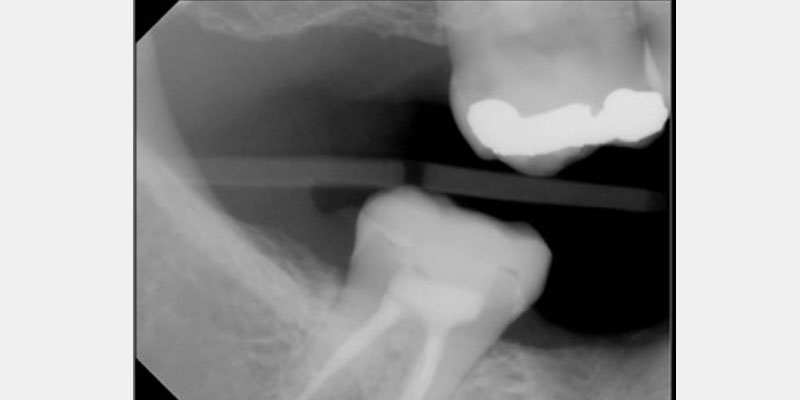

Compromised endodontically treated teeth with minimal tooth structure can be challenging to restore. Traditional approaches of a prefabricated post and core or cast post and core have worked well. However, there are instances where a post and core may be especially difficult or not feasible for a tooth. The endocrown provides an alternate approach for saving and restoring these compromised teeth.

Since the early work on endocrowns was published by Bindl and Mormonn, a host of other studies have looked at preparation design for endocrown restorations. When preparing a tooth for an endocrown, a 2.0 mm occlusal reduction with extension into the pulp chamber is required.

The literature suggests a shoulder and a chamber finish line2, 3, 4 with the extension into the pulp chamber protruding approximately 2.0 mm into the chamber.5 Minimal retention is present, and thus, these restorations must be bonded in place with resin cement.